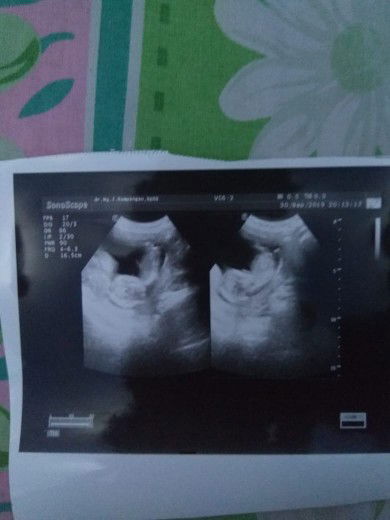

Cerita ah,wkt hamil pertama gak pernah yg ngalamin mual,muntah,pusing,atau lelah semua berjalan baik² aja,pas hamil anak kedua ini berbagai keluhan byk bgt tp bersyukur hanya smpe 12week utk mual muntah nya, kelelahan,dan badan blkg sakit msh sampe skrg terasa bahkan tiap mlm pipis trus berkali²,tp utk mknan smua udah bs masuk apa aja di mkn kaya mie instan,durian,jengkol apa ajalah dimakan krna dr sebulan smpe 3bln gak mau mkn tp tetap di jaga diwkt mau lahiran nanti stop jengkol dan mie instan hehe bersyukur kmren USG baby nya sehat, aktif,dan bbj nya cukup sesuai usia kehamilan...?

15week

Seneng cepat besar BBJ 100gram normal kata dokter dan aktif skli baby ku